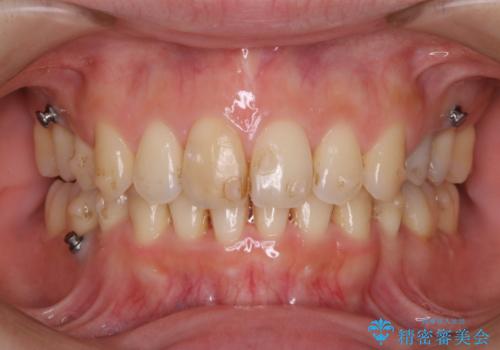

着色が多くアタッチメントの周りや裏側に付いていました。

写真よりも実物の方が、着色が付いており患者様もとても気にされていた。

仕事上、マウスピースをはめたままコーヒーを飲む機会が多く着色してしまったそうです。